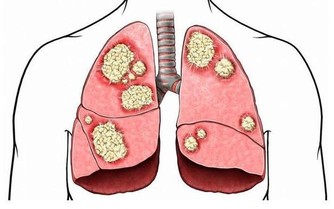

對於大多數宮頸癌患者來說,疾病的第一個徵兆並不是奇怪的疼痛或異常的感覺。在早期階段,確實沒有任何症狀。然而就像大多數癌症一樣,早期階段也是治療結果最好的時候。這就是為什麼美國疾病預防控制中心和美國癌症協會都建議所有女性在21歲時開始接受定期巴氏試驗。如果巴氏檢測結果顯示異常,這時候做手術,往往非常成功。

但另一方面,如果你能注意到一些細微的症狀,就可以盡可能早得捕捉到癌症的跡象。下面我們就來了解一下: